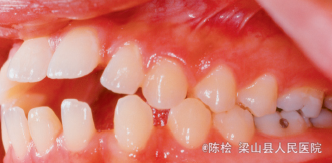

随访 讨论

对于开合病人,光是压低后牙可能效果不是很好,应把改不良习惯的装置一同考虑进去才能达到事半功倍的效果。该装置既包含腭刺又焊有TPA,一举两得,值得推广。